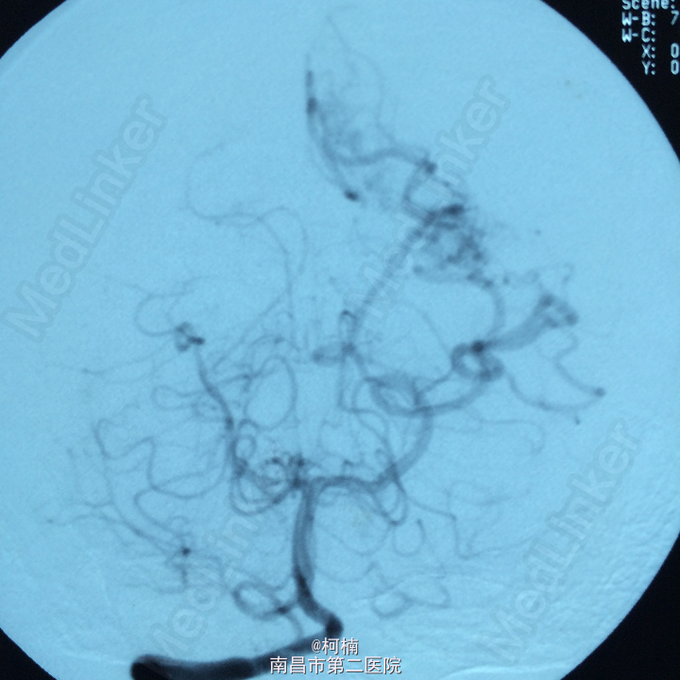

诊断:脑动静脉畸形 处理:予急诊行DSA检查,提示脑动静脉畸形,予行血管内栓栓塞治疗